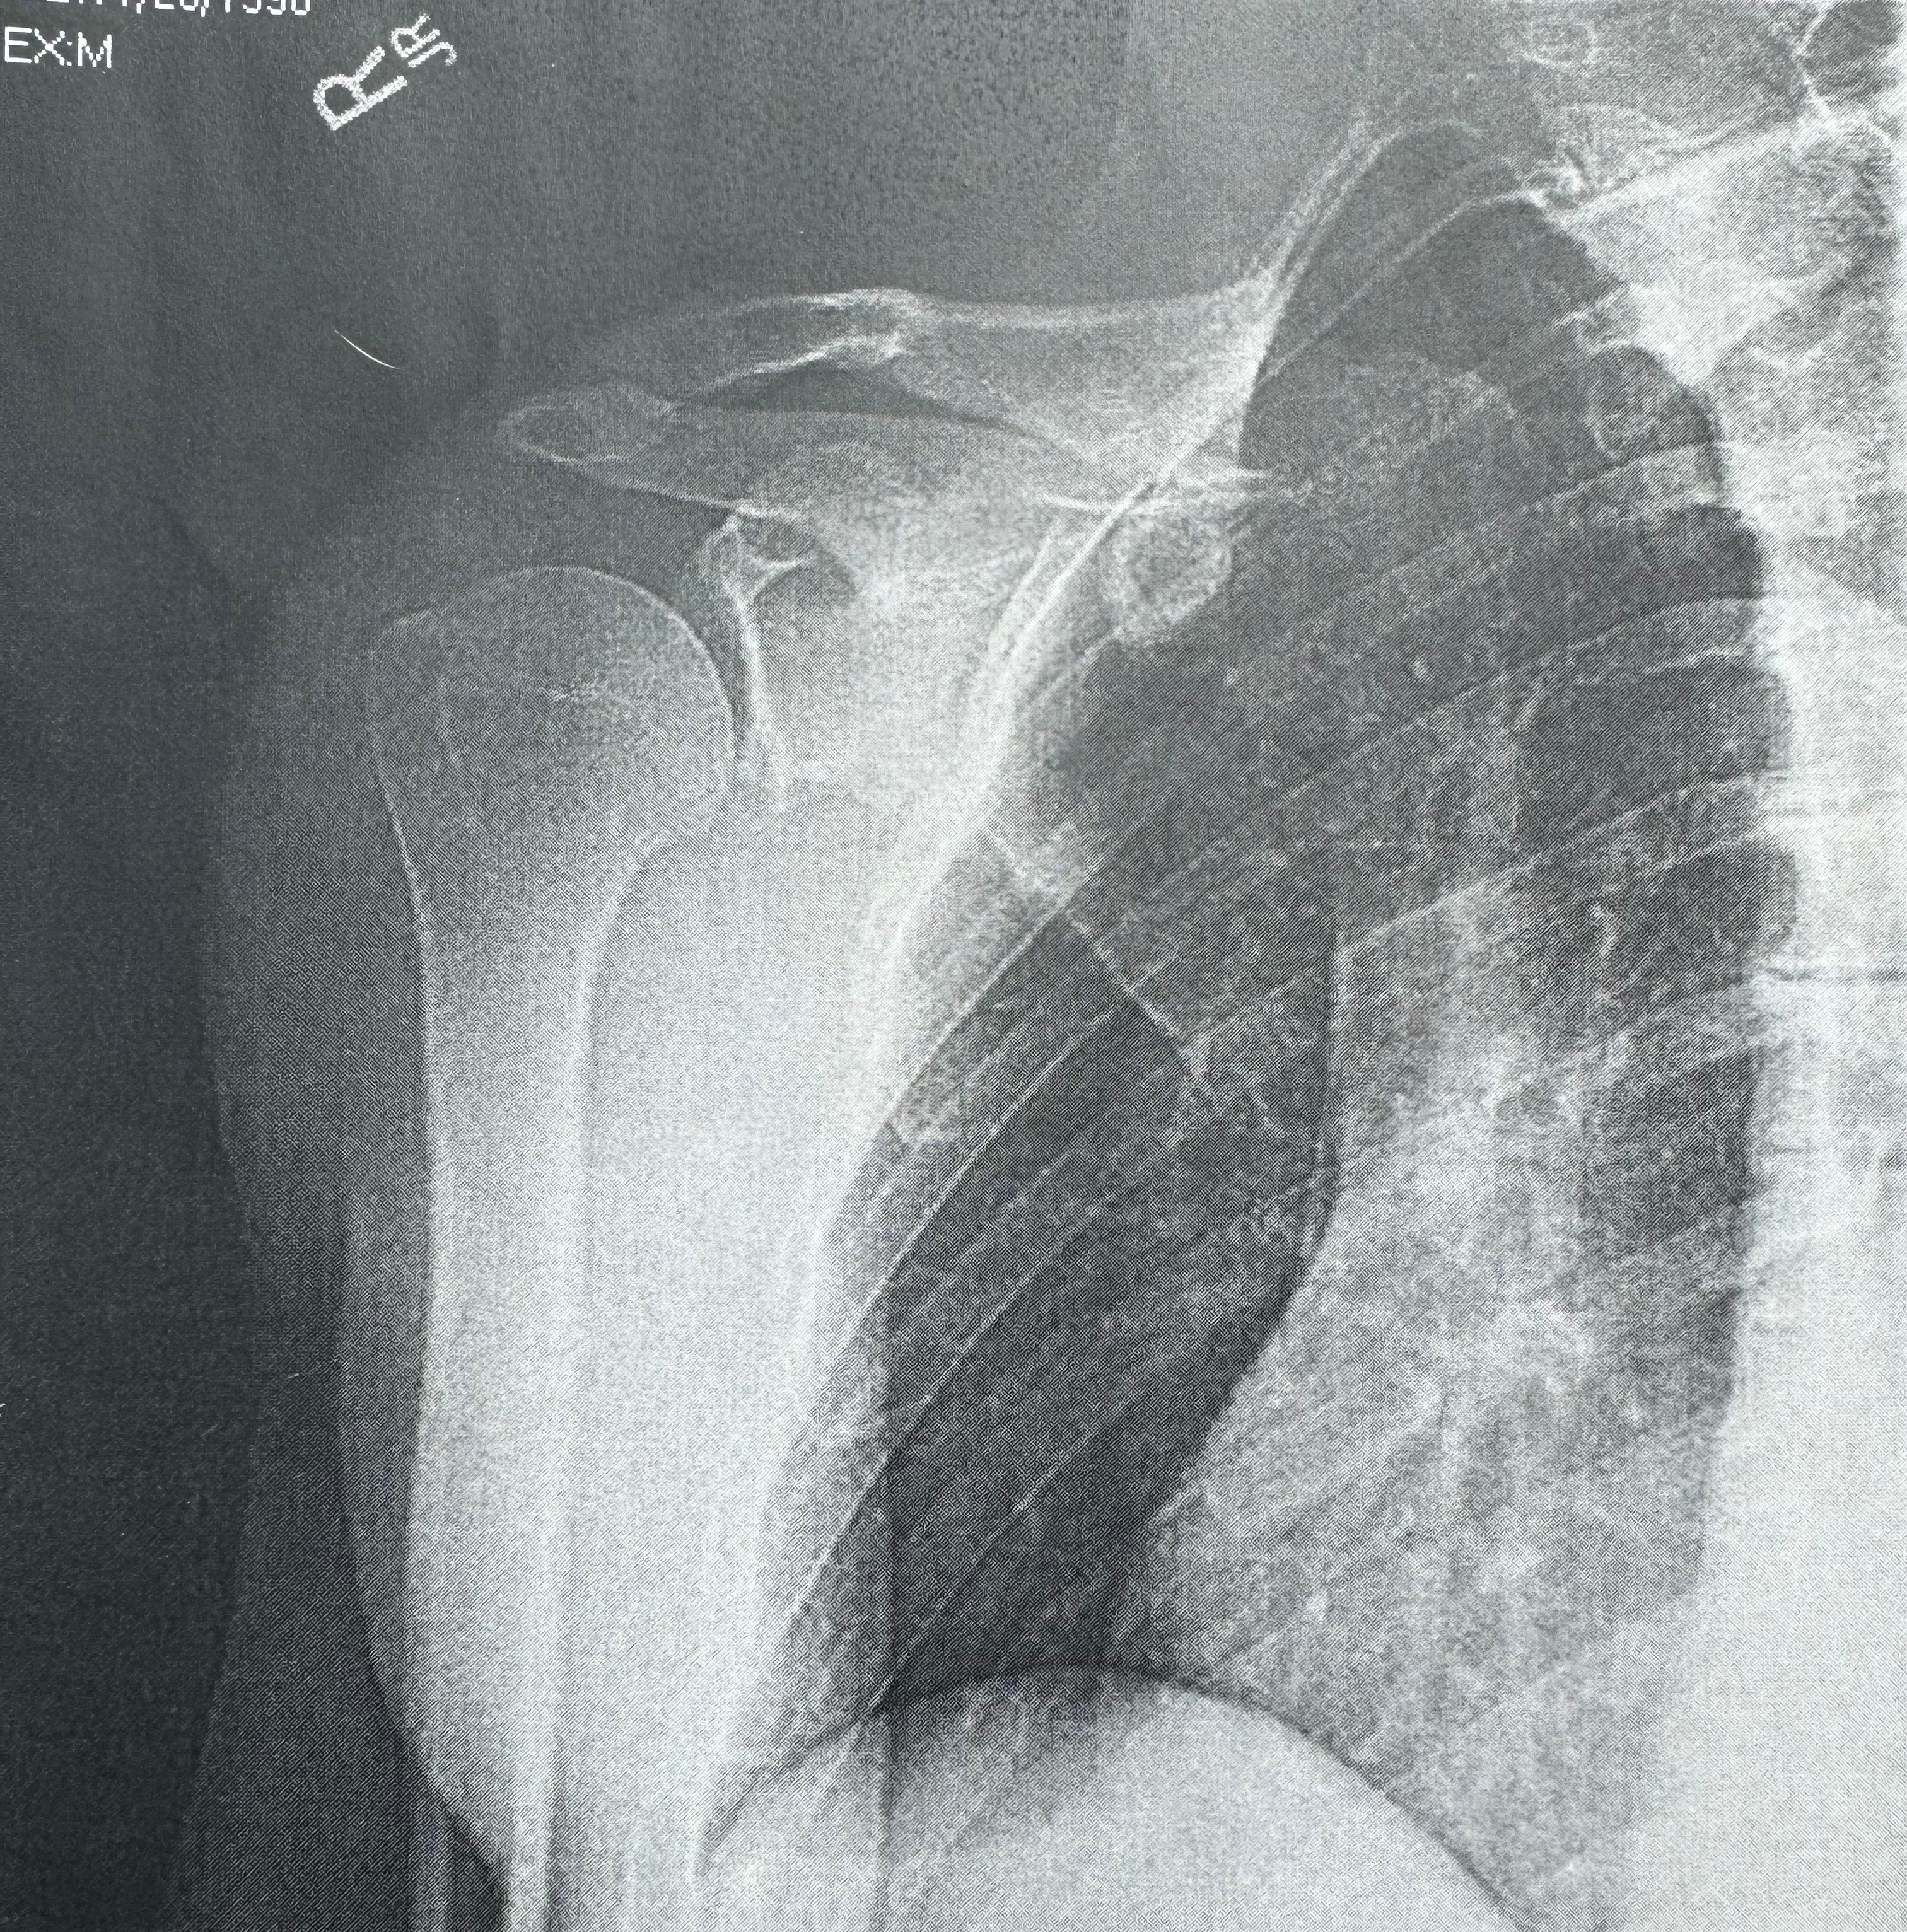

On 11/10/25 the front wheel on the scooter I was riding popped, causing me to fall into the street at roughly 15mph and fracture my right shoulder socket (glenoid fracture) which required immediate surgery. As many of you know I've been self-employed as a medicine facilitator for years, which means I do not have any form of health insurance. This unexpected ER visit and shoulder surgery have left me with a significant financial burden that I am going to be paying for entirely out of pocket.